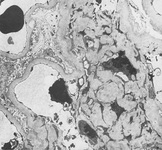

Diabetic kidney disease

Diabetic kidney disease: at 12 o'clock - early Kimmelstiel-Wilson nodule, a rounded form of mesangial expansion

From the collection of Dr Raoul Fresco; used with permission